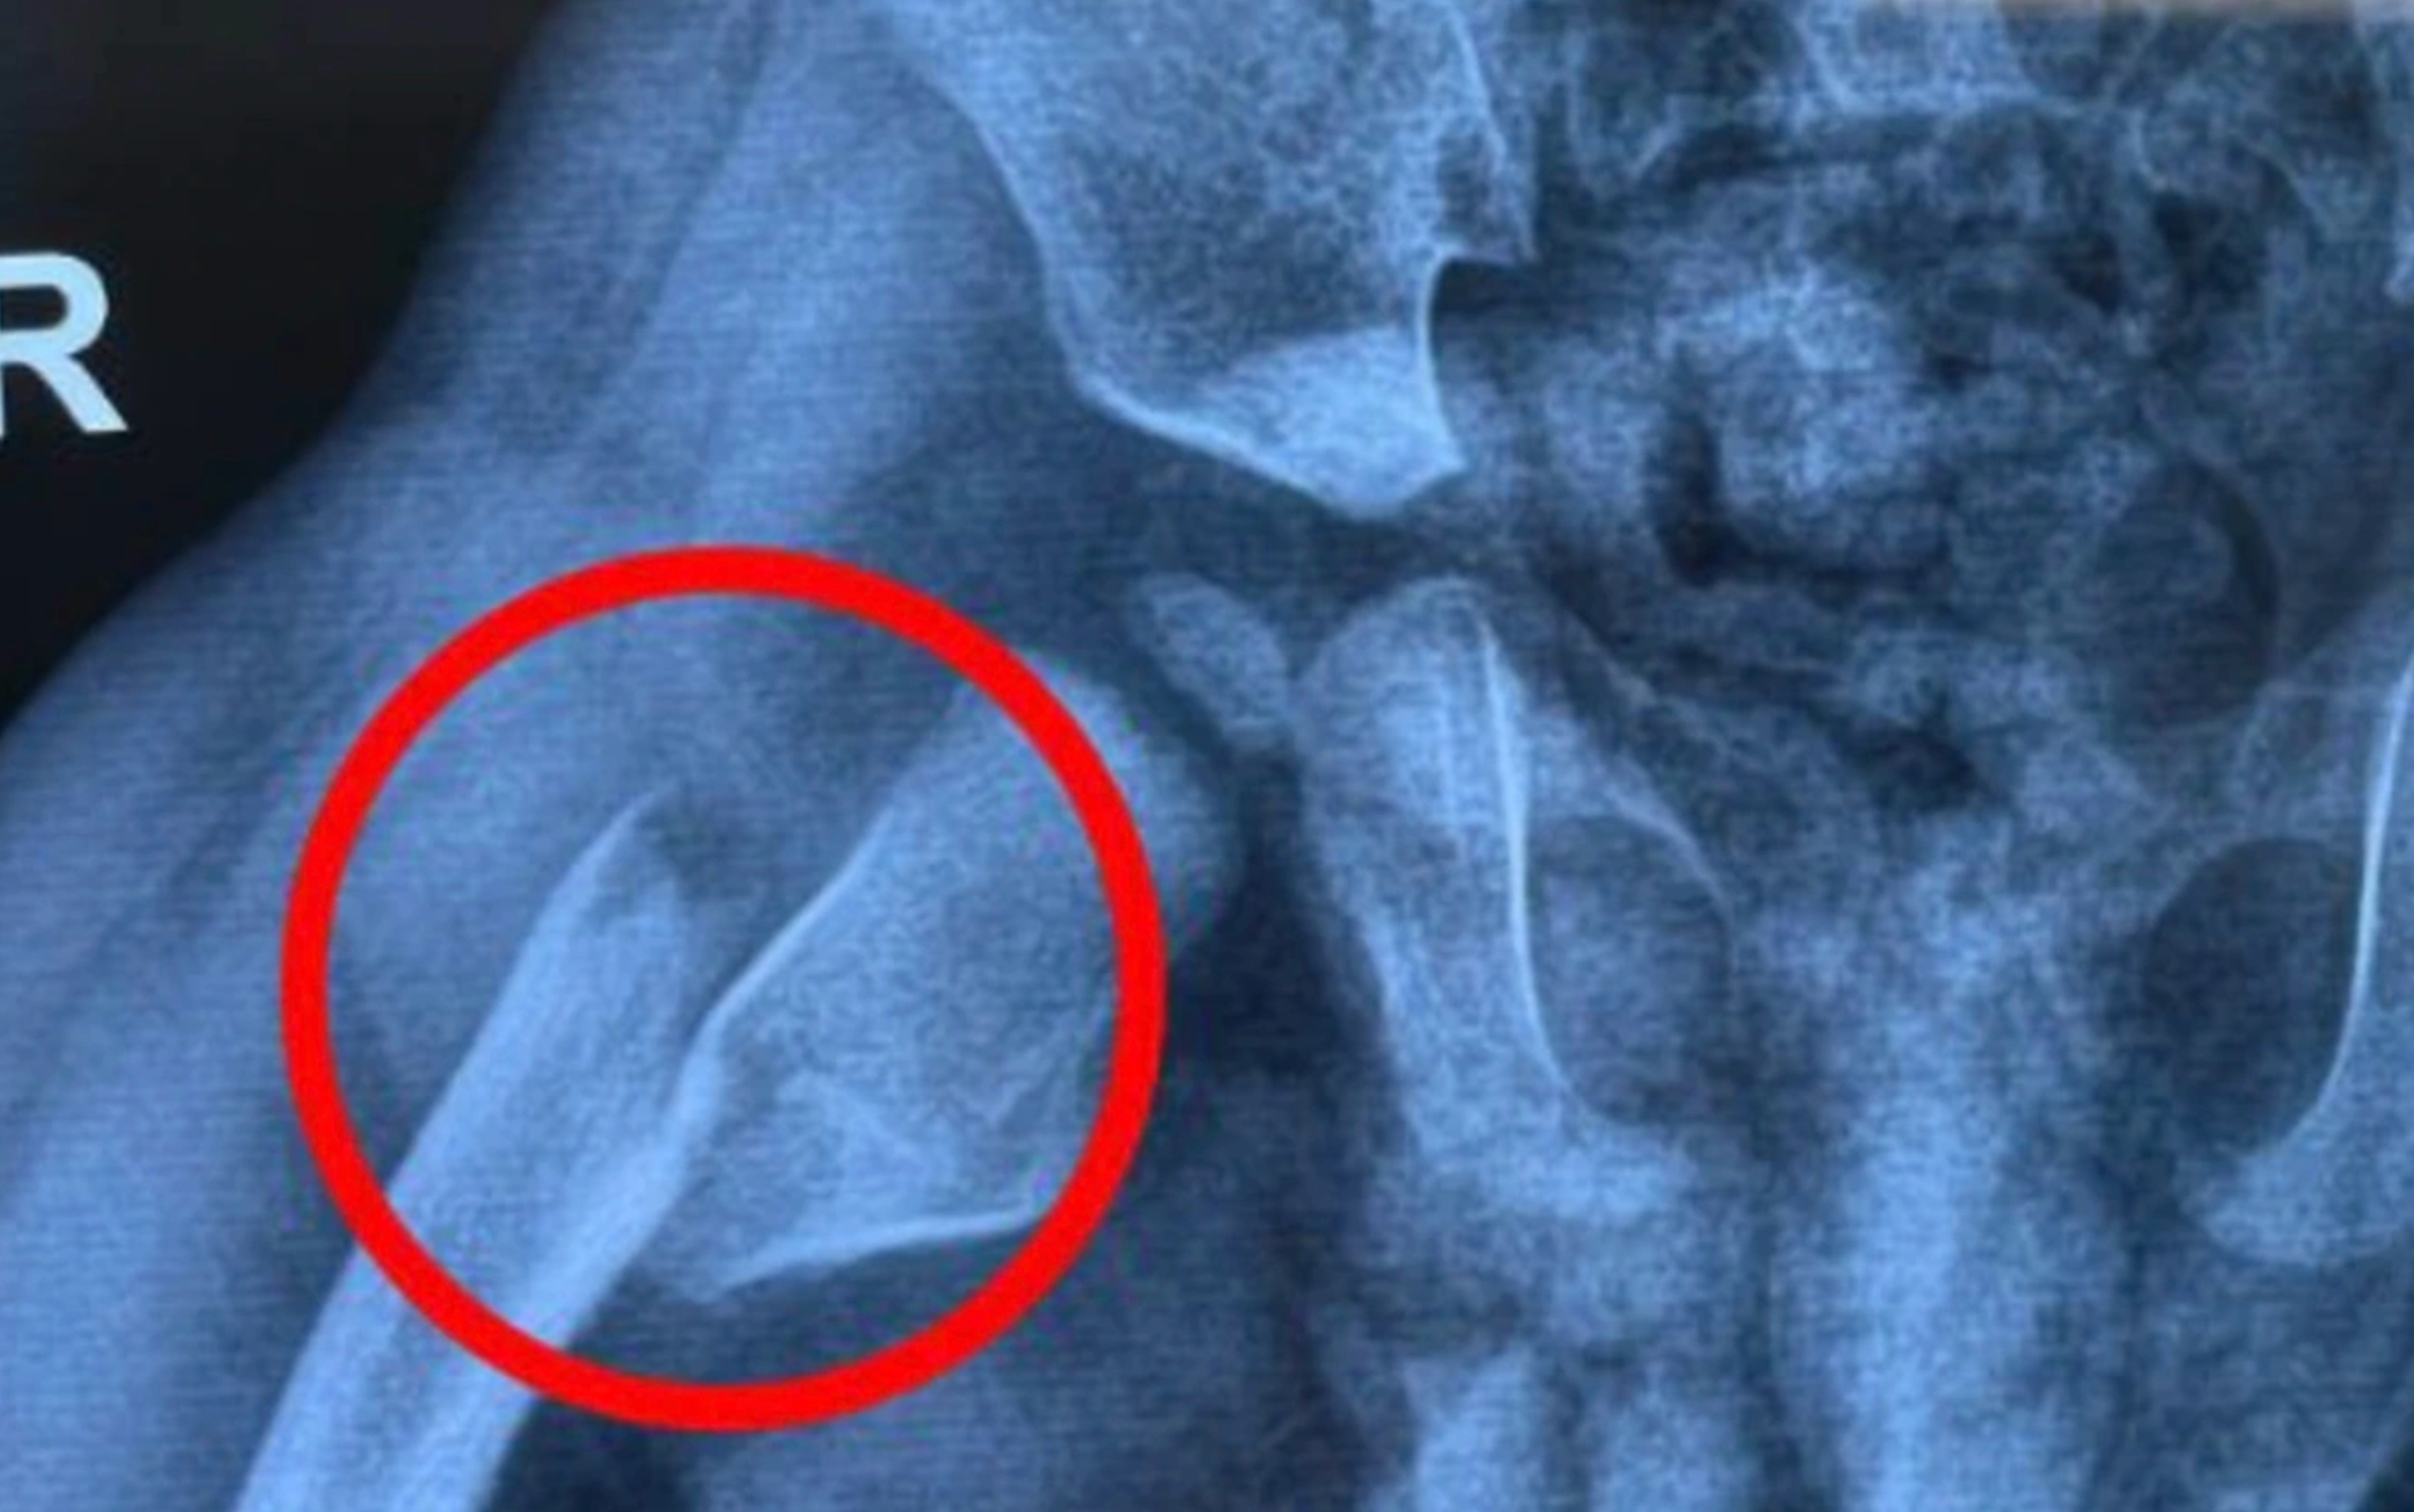

Sau khi khám và chụp X-quang, bác sĩ chẩn đoán bé L. bị gãy xương đùi phải, hai đầu xương gãy di lệch. Bé L. được bác sĩ chỉ định điều trị bằng phương pháp bó bột toàn thân, từ cổ chân đến ngực.

Kết quả chụp X-quang vùng đùi phải của bệnh nhi tên L. (1 tuổi) với hai đầu xương gãy di lệch. (Ảnh: BV)

Thạc sĩ, bác sĩ Nguyễn Xuân Trường, Trung tâm Chấn thương Chỉnh hình cho biết, vị trí gãy gần khớp háng, trong khi trẻ nhỏ chưa có ý thức kiểm soát vận động, dễ co duỗi và di chuyển toàn thân. Bên cạnh đó, hệ xương và cột sống của trẻ nhỏ vẫn còn yếu, cần được cố định để đảm bảo quá trình hồi phục. Việc bó bột dài sẽ giúp bệnh nhi cố định được toàn bộ, hạn chế chuyển động phần chân, thân đồng thời bảo vệ khớp háng, xương sống tốt hơn.